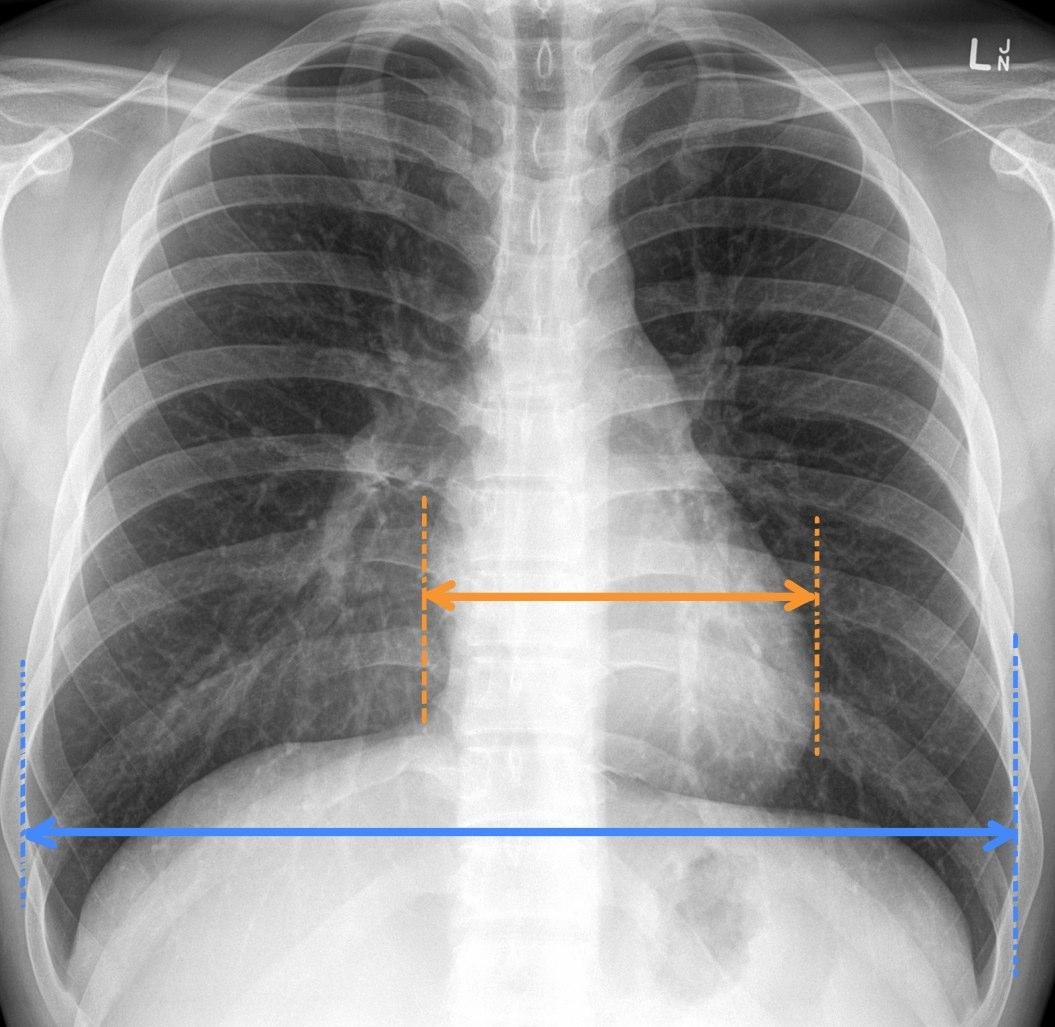

Cardiothoracic ratio

Cardiothoracic ratio: widest transverse diameter of the heart compared with the widest internal diameter of the rib cage (from inside of rib to inside of rib at the level of the diaphragm)

In most normal adults at full inspiration, the cardiothoracic ratio is less than 50%

Normal CT ratio should be less than or equal to 50%

Cardiothoracic ration